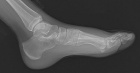

R.T. - 15 year old female noticed left dorsal foot mass two months ago; it is slightly tender to touch and bothers her with full plantar flexion, she also noticed some discoloration of the skin in the area

Zoom image: Radiological image Radiological image.